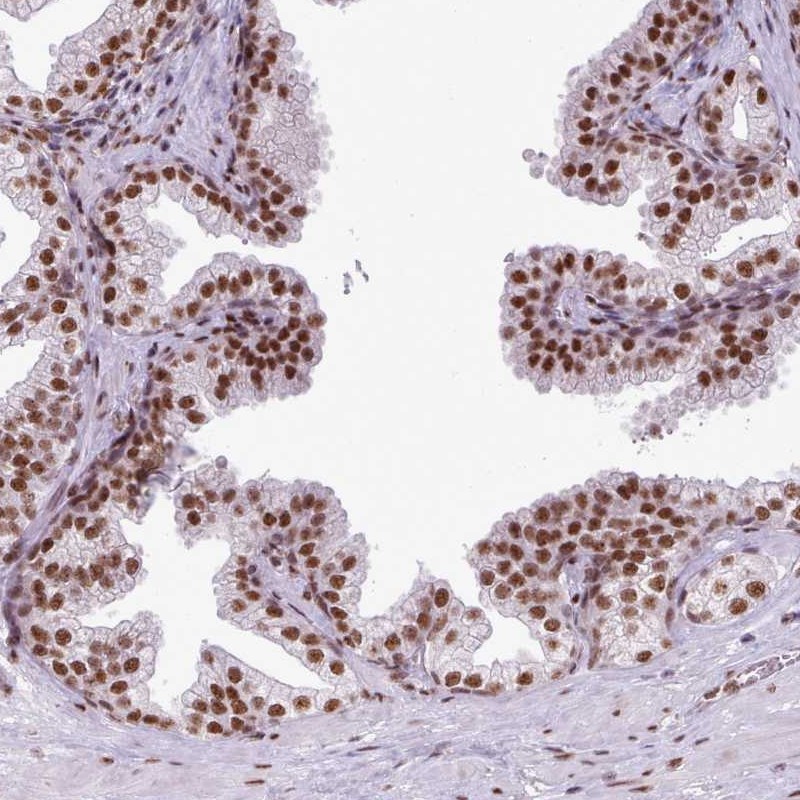

Immunohistochemical staining of human prostate shows strong nuclear positivity in glandular cells.